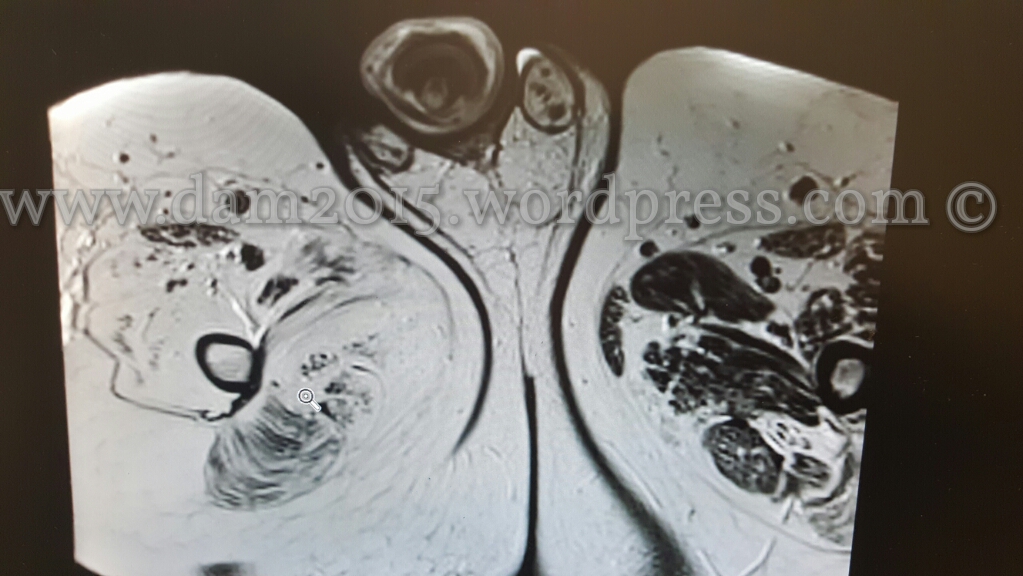

RM DEL PENE CON MDC – l’indagine ha dimostrato marcato edema sottocutaneo con aree fluide ed emorragiche nel contesto a carico del pene, decisamente più marcato a livello del III inferiore.